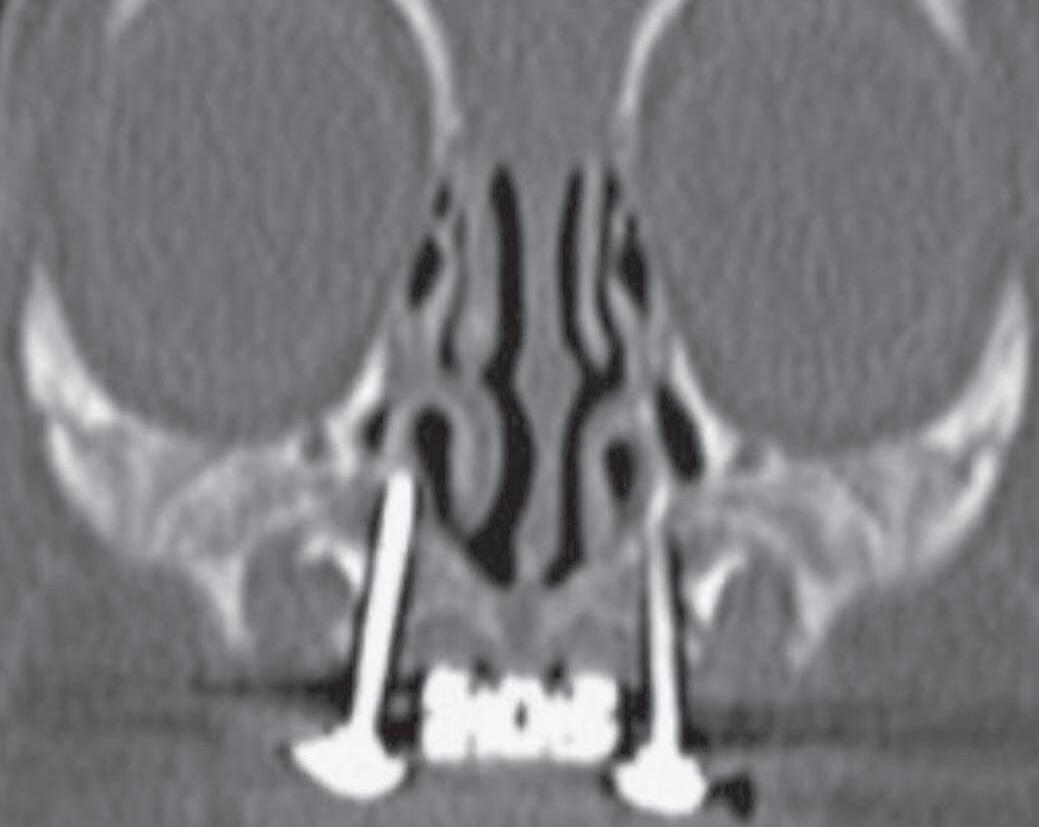

A tomografia computadorizada (TC) é o exame de escolha: valores abaixo de 11 mm são considerados sugestivos. Alguns autores mais rigorosos consideram o limite inferior de 8 mm (Fig. 1-1). A TC também avalia malformações associadas e estruturas como lâmina cribriforme e base do crânio.9 O diagnóstico diferencial deve incluir atresia de coanas, cistos, encefaloceles e tumores. A endoscopia nasal é útil para localização da obstrução.5,10

Além da correção esquelética, a ERM proporciona alargamento da base nasal, promovendo a redução da resistência ao fluxo aéreo e, consequentemente, aumento da ventilação nasal (Fig. 1-4).

9. Ao final da expansão, nova TC pode ser realizada para mensuração objetiva do ganho de espaço aéreo (Fig. 1-4), além da avaliação clínica (Fig. 1-8).

Apesar da eficácia da técnica de desgaste ósseo na abertura piriforme, seus potenciais riscos e complicações levaram ao aparecimento de outras opções terapêuticas. Vários estudos demonstraram que a atresia é maxilar, não se limitando ao piriforme, mas se estendendo por quase toda a cavidade óssea nasal.12,14 A expansão rápida da maxila, com dispositivo disjuntor e ancoragem esquelética por meio de miniparafusos, com sua fundamentação anatômica, biomecânica e funcional, é menos invasiva, proporciona uma expansão tridimensional eficaz ao longo de toda a fossa nasal, produzindo uma melhora funcional consistente nas vias aéreas superiores, que se mantém ao longo de todo o período de crescimento craniofacial (Fig. 1-9). Assim, a ERM credencia-se como técnica de escolha no tratamento da ECAP.15